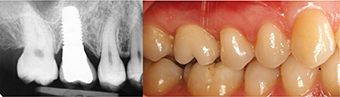

Cliché panoramique d’une femme de 45 ans qui demande le remplacement de la deuxième molaire mandibulaire droite (47) par une couronne sur implants. La patiente est adressée au spécialiste pour avis chirurgical et mise en place de la racine artificielle. Plusieurs autres dents sont absentes et non remplacées. Des déplacements dentaires conséquents sont observés, notamment les égressions des 16 et 17.

photo 5-

Un implant a été incorporé en 47 par le praticien, sans qu’aucune correction des malpositions soit envisagée. après ostéo-intégration, une couronne sera installée par l’omnipraticien.

photo 6-

Cinq ans après la mise en place de l’implant, la patiente retourne vers le chirurgien pour avis, suite aux dévissages récurrents de la couronne. un nouveau cliché panoramique permet de constater une perte sévère du niveau osseux autour de l’implant. La zone exprime du pus à la pression digitale.

photo 7-

L’observation clinique montre qu’aucun aménagement des espaces n’avait été mis en œuvre pour restaurer l’espace naturel de la couronne de 47. L’égression de 17 occupe la place de 47. La patiente a conservé les modèles de travail. La mise en place de la couronne sur ce modèle montre que la couronne de 47 n’est pas dans le plan d’occlusion adéquat. Ni la position du point de contact ni le profil des embrasures sont en conformité avec les exigences fonctionnelles et prophylactiques les plus élémentaires. La fracture de la céramique et le développement d’une péri-implantite en sont les conséquences inévitables.

photo 8-

La situation péri-implantaire idéale est réalisée lorsque l’espace prothétique et le volume osseux résiduels permettent de placer la racine artificielle dans une situation qui favorise la construction d’une couronne dont les contours répondent à toutes les caractéristiques d’une dent naturelle, à savoir l’émergence gingivale, les embrasures, la face occlusale, les angles de transition et les points de contact.